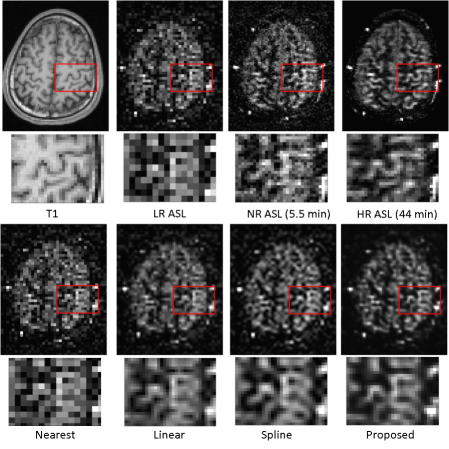

In the first experiment, the network was trained using the LR ASL image as the training label. The super-resolution results were compared with the nearest interpolation, linear interpolation, and spline interpolation results, as shown in Fig. 2 (sagital view) and Fig. 3 (transaxial view). It can be seen that images of the proposed method have a good visual appearance with clear boundaries and low image noise. The quantitative results of PSNR and SSIM are shown in Table. 1. One interesting observation is that when using NR ASL image as the reference image, both linear and spline interpolation have better PSNR and SSIM than the proposed method. However, the proposed method achieves the highest PSNR and SSIM when using 44-min HR ASL image as the reference image. As the NR ASL image is still noisy and does not have as many details as the HR ASL image, this conflicting conclusion actually proves that the proposed method does utilize the structure information from T1-weighted image which can not be observed from the NR ASL image.